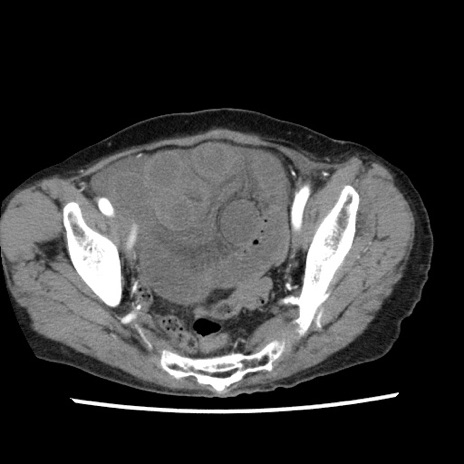

症例1(横断像)

【症例】80歳代女性

【主訴】腹痛

【現病歴】8時間前から腹痛あり来院。

【既往歴】糖尿病、脂質異常症、子宮体癌にて子宮全摘術

【身体所見】意識清明・会話良好だが腹痛で苦悶様、全腹部にわたって反跳痛と圧痛あり

【データ】WBC 13600、CRP 0.14、LDH 224、CK 90